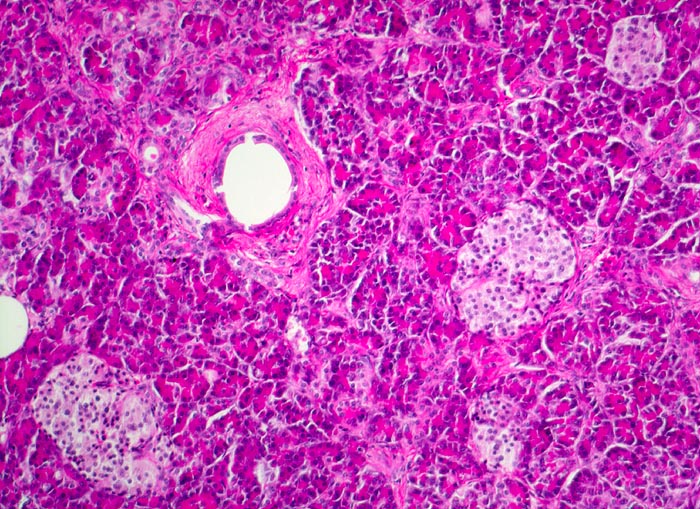

Die Nekrosen des interlobulären Gewebes und der interlobulären Gänge bei ethylischen Pankreatitisschüben führen primär zu einer interlobulären Fibrose und interlobulären Gangstrikturen. In den betroffenen interlobulären Gängen führt der Sekretstau zur Konkrementbildung (verkalkte Proteinpräzipitate). Wie bei einer chronisch obstruktiven Pankreatitis kommt es in den unvollständig drainierten Läppchen zu einer Atrophie der Azini verbunden mit intralobulärer Fibrose. Letztere Areale enthalten schliesslich nur noch Reste unregelmässig verteilter Gänge, Inseln, Nerven und Gefässe. In vielen Fällen lassen sich extrapankreatische Pseudozysten gefüllt mit nekrotisch-hämorrhagischem Detritus in der Nachbarschaft der fibrosierten Bezirke nachweisen.

Atrophie des exokrinen Pankreas.

Erhaltene Inseln und Gangstrukturen.

Rechts oben ist eine partiell vom Rand her durch Granulationsgewebe organisierte lytische Fettgewebsnekrose erkennbar. Diese ist Folge eines akuten pankreatitischen Schubs.